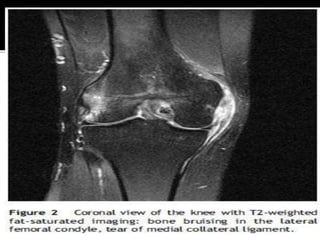

 If we take an example of bone brusing on

such condition where you can see bone

bruising is ACL

 In ACL Rupture , there is concurrent

associated bone bruising at the femoral

condyle and or tibial plateau

 A Xray would indicate whether there is a

fracture or no

 But the current gold slandered is MRI to

check whether the bone has a bruise or no